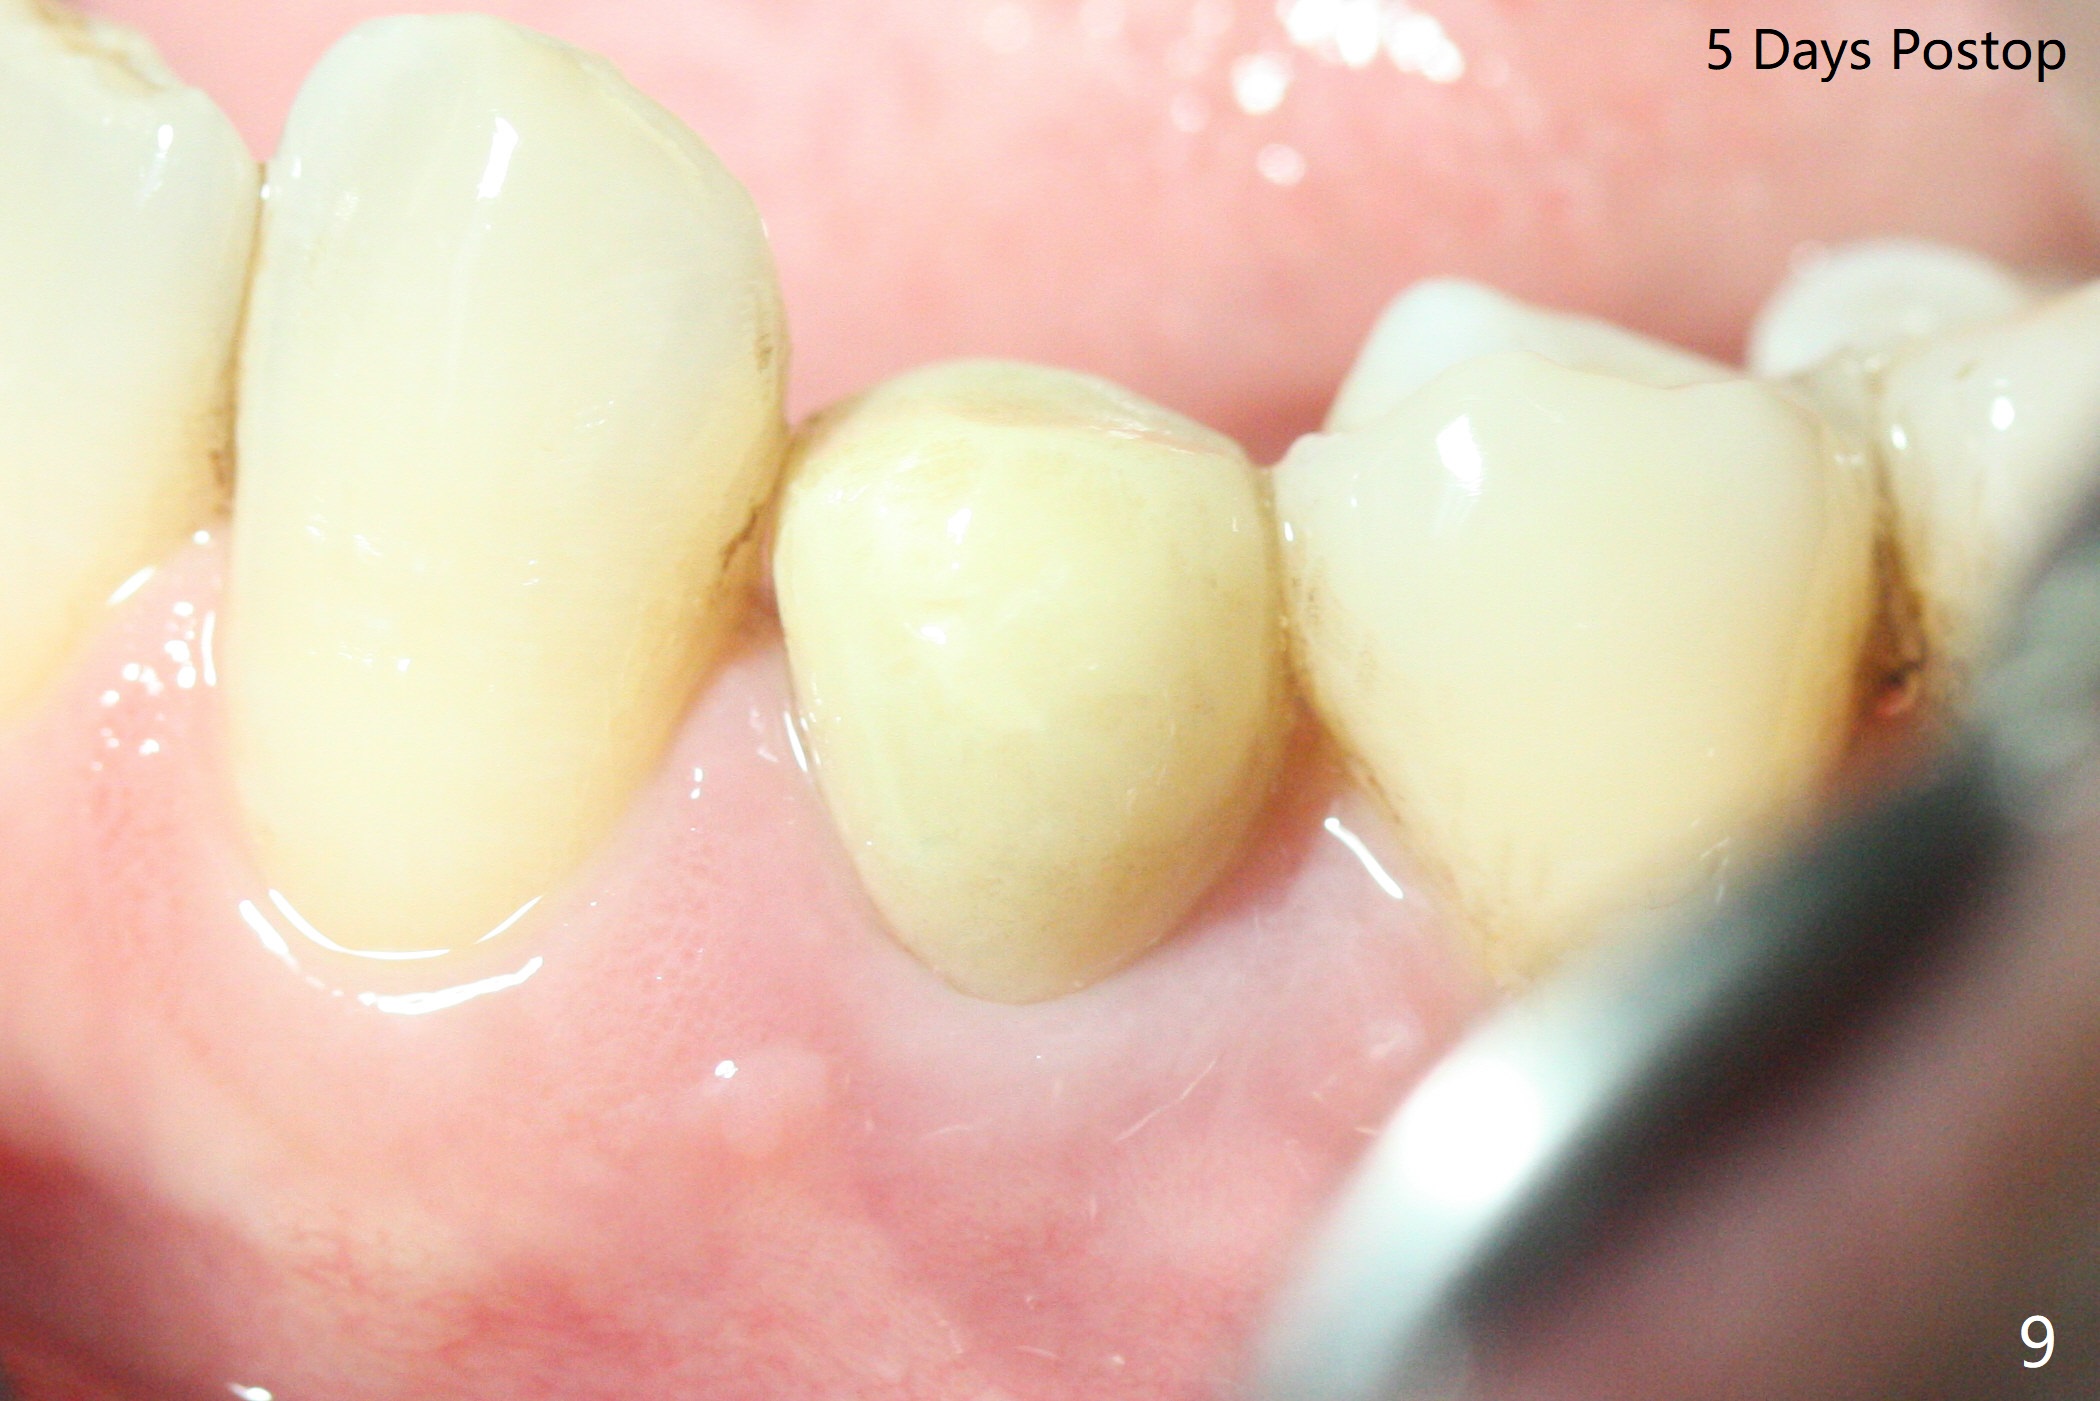

Three months post guide fabrication (coronavirus outbreak), the patient with loose post/crown returns for #21 extraction and immediate implant with guide (Fig.1 (*: post space)). In fact the root stump is flattened with diamond bur and 9 mm bone trimmer with guide before point drill. When the osteotomy finishes with 3.5x13 mm drill (under drilling with 10.5 mm offset), it has deviated buccal (Fig.2, 3,4); the outline of the bone trimmer mark is labeled by arrowheads in Fig.2. It appears that the center of the bone trimmer is dictated by that of the post space, as compared to Fig.1 *). When the root is removed except buccal shield (assuming that the deviation was due to the uneven surface of the root stump), the osteotomy is redone with guide, but remains buccal. Finally with buccal shield removal, a new lingual osteotomy is created free hand for a 4.5x11 mm implant (Fig.5) with 2-3 mm buccal gap for bone graft (Fig.6 * (literally)). In brief, bone trimmer also deviates according to resistance, basically irrelevant to the guide sleeve. The immediate provisional is intentionally removed 5 days postop to check whether a piece of gauze is retained in the socket as a gingival retraction cord for temporary crown fabrication; the buccal gap is kept with bone graft (Fig.7 *). No foreign body is in place. The margin of the abutment seems quite subgingival (Fig.8 *), but re-trimmed and polished provisional looks harmonious with the surrounding gingiva and the opposing dentition (Fig.9,10). The patient returns for prophy 2 months postop; the immediate provisional is removed for trimming and polishing. The bone graft seems to be integrated into a part of the gingiva (Fig.11 >). The abutment cuff appears to be too short.